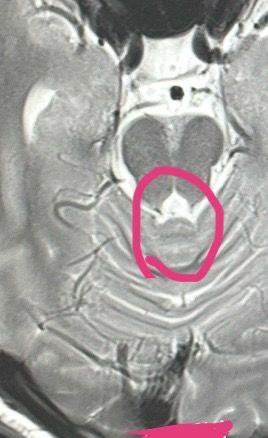

그 이후에 증상이 나아지지 않아 ct도 찍었는데 아래 사진처럼 이상이 있다는 소견과 함께 안구 운동 과 관련하여 발달이 덜 된 것 같다고 했습니다. 그래서 신경외과에 가서 진료를 보았는데 선천적으로 그렇게 된 것 같고 이게 어지러운 것과는 연관이 있다고 보기 어려울 것 같다고 했습니다. 그래서 결국 원인은 못 찾은채로 하던대로 약 먹었고 나아지는 듯했습니다.

정말 ct에서 나온 이상 소견이랑 어지러움이랑 관련 짓기 어려울까요..? 그리고 왜 그런 걸까요..? 저체중(169.48)이랑도 관련이 있을까요? 의사 선생님께서 운동을 하라고 하셨는데 더 심해질까봐 운동할 엄두가 안나요. 이 상태에서 운동해도 괜찮을까요?

• 1번 째 사진

CT 관련해서 더욱더 자세한 분석이나 새로운 시선을 원하시면 영상의학과 전문의에게 의뢰하셔야 합니다.

CT에서의 이상 소견(안구 운동 관련 미세 발달 문제)은 어지러움의 일부 보조적 요소일 수는 있어도 주된 원인으로 보기는 어렵다는 기존 설명도 일리가 있습니다.